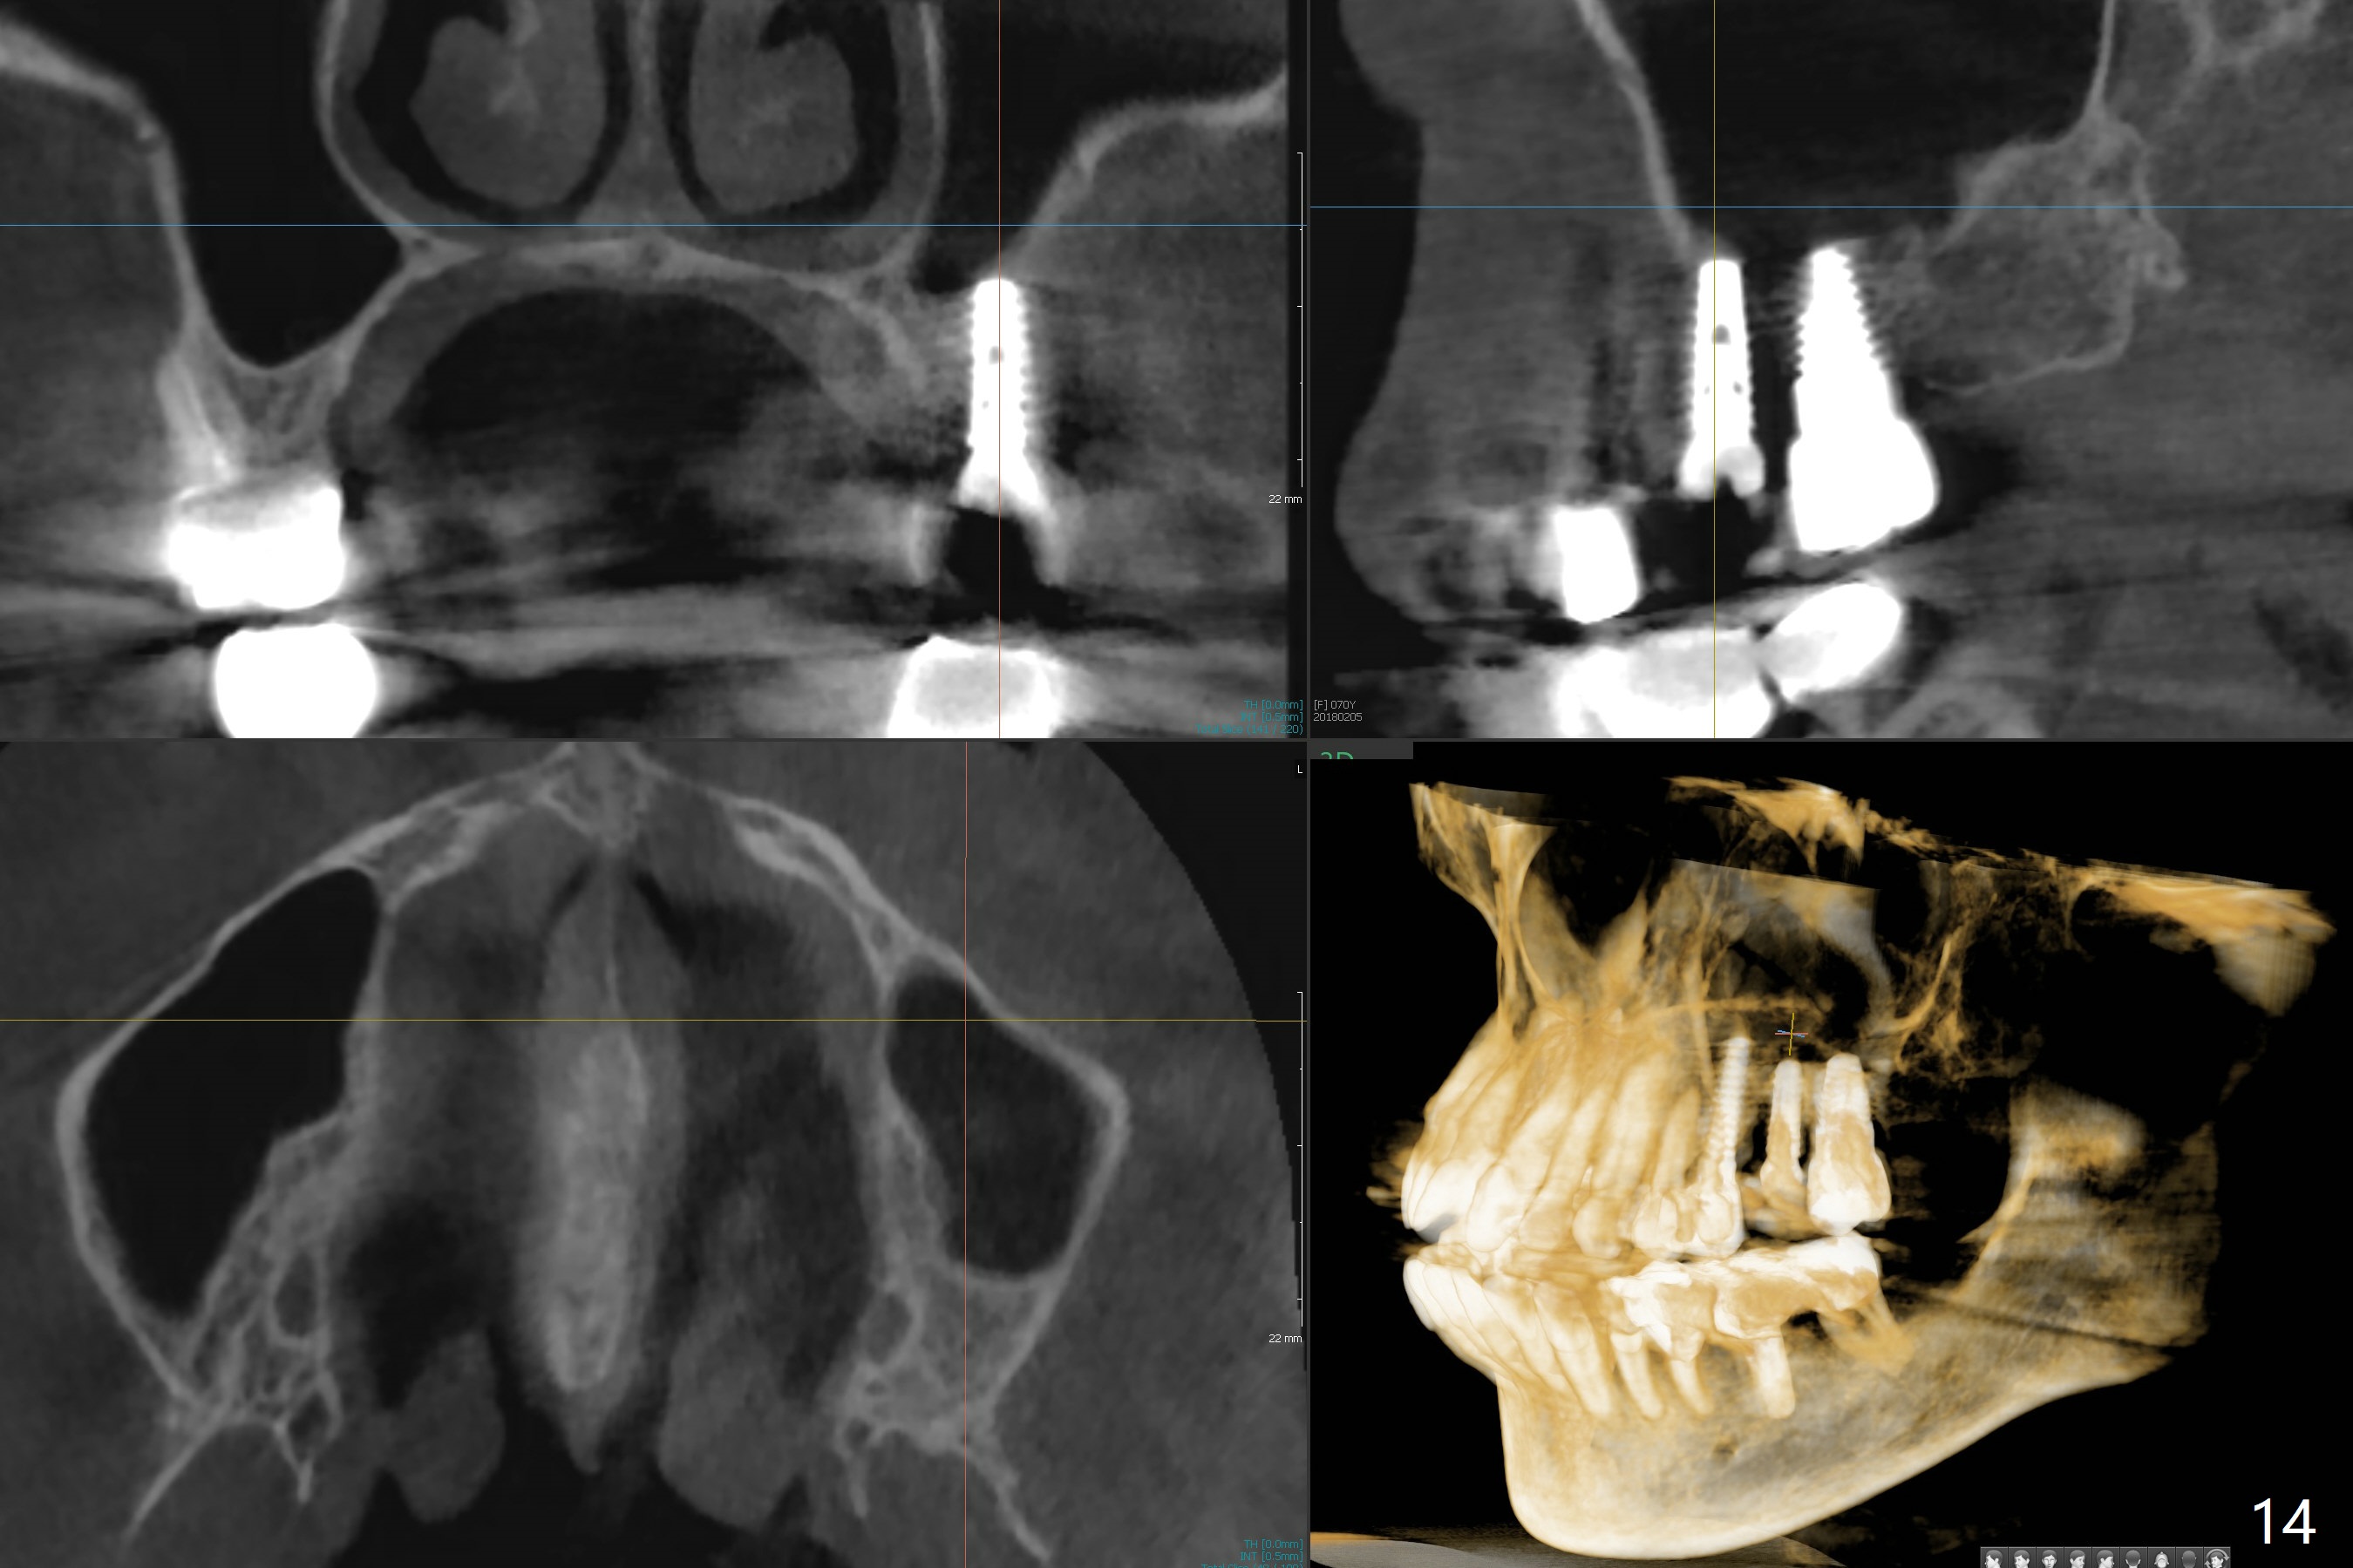

Initial osteotomy in the septum of the tooth #14 is 9 mm, approximately 2 mm from the sinus floor (Fig.1).  Subsequent osteotomy depth is 11 mm, followed by insertion of a 4.5x11 mm dummy implant (Fig.2).  After use of Magic Drill (MD) 4.8 mm for 9 mm, a 5x11 mm IBS implant is placed with sinus lift without additional bone graft (Fig.3 *).  In contrast, autogenous bone (from MD) and Vanilla Graft are meticulously placed in the remaining socket (+) before and after placement of a 6.5x5.7(2) mm abutment.  An immediate provisional is fabricated to close the sockets.  There is buccal tenderness 1-3 months postop.  There is distopalatal implant thread exposure.  A healing abutment (5.5x2 mm) is placed.  CT confirms thin buccal plate (Fig.4,5).  It appears that the implant should have been as palatal as possible.  The tenderness remains for the next 2 weeks.  When the healing abutment is removed, the implant seems to have been placed shallow, ~ 1 mm subgingival (Fig.6).  With local anesthesia, the implant is reversed to clean the coronal threads with Titanium brush and copious irrigation (Fig.7).  The implant is then placed ~4 mm subgingival (Fig.8) and slightly subcrestal (Fig.9,10).  It appears that the postop bone loss (Fig.9 *, as compared Fig.1,2) makes the implant look to be placed too shallow.  When the implant is being placed deeper, the buccal plate feels intact.  The early periimplantitis is apparently due to postop bone loss more than buccal placement, although certain degree of buccal bone resorption must occur.  A 6x4 mm healing abutment is placed.  Left facial swelling develops 2 days post implant elevation (Fig.11,12, as compared to preop (Fig.13)).  The left maxillary sinus cloud (Fig.12) appears to be a false positive finding, since the same feature exists prior to implant elevation (Fig.13).  Both sinuses look clear prior to implant elevation (Fig.14).  Amoxicillin switches to Augmentin and Flagyl, since the patient is reluctant to have the implant removed.  Finally the sinus infection is under control.  The patient feels left facial swelling 9 months postop (5 months post elevation) and reports left nasal discharge ~ 1 month earlier.  There is mild buccal plate tenderness.  The implant seems to be buccally placed (Fig.15,16), although there is no significant change radiographically (Fig.17).  The implant is removed with bone graft (Fig.18 *).  To avoid complication and failure, an immediate implant at the upper 1st molar should be short and placed deep.